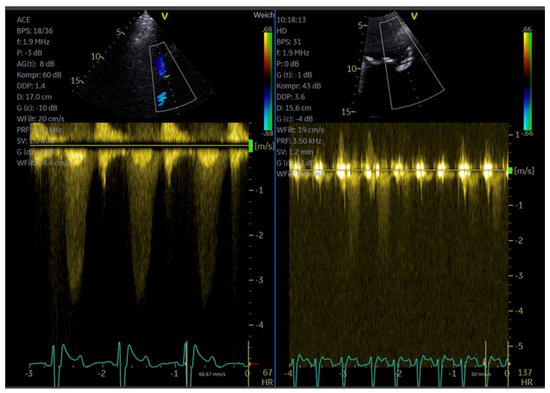

| Flow assessment in epicardial coronary arteries (Color and PW Doppler) |

| Aortic stenosis (CW Doppler) |

| Pulmonary venous flow (PW Doppler) mitral regurgitation |

| Tricuspid regurgitation (CW Doppler) for measurement of PA pressure * |

| Imaging method | CW Doppler for aortic stenosis/tricuspid regurgitation PW-Doppler: for pulmonary–venous flow |

| Imaging planes | Same as for non-contrast Doppler imaging, the enhanced color Doppler signals facilitate the alignment of the cursor for spectral Doppler measurements |

| Contrast application | Bolus injection, the recordings can be performed during the washout after recordings for assessment of LV function |

| Typical findings | Intensive Doppler spectra Consider reduction in gain or power. |

| Alternative imaging | TEE, cardiac MRI |